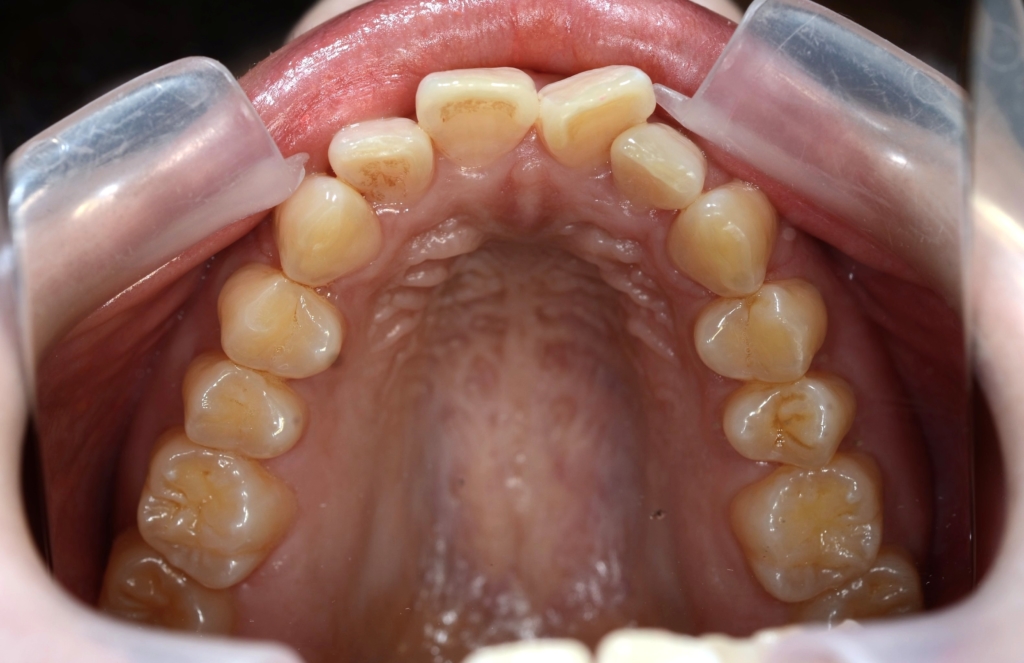

【Before】

レントゲン写真を確認すると、

この患者さんの場合、

【診断】

#1.上顎前突

#2.顎と歯の大きさの不調和による叢生

#3.ガミースマイル

と診断しました。

*歯並びの写真で見ると「出っ歯」であるとは分かり難いですが、頭部全体のレントゲン写真を見ると、出っ歯であることがハッキリと分かります。